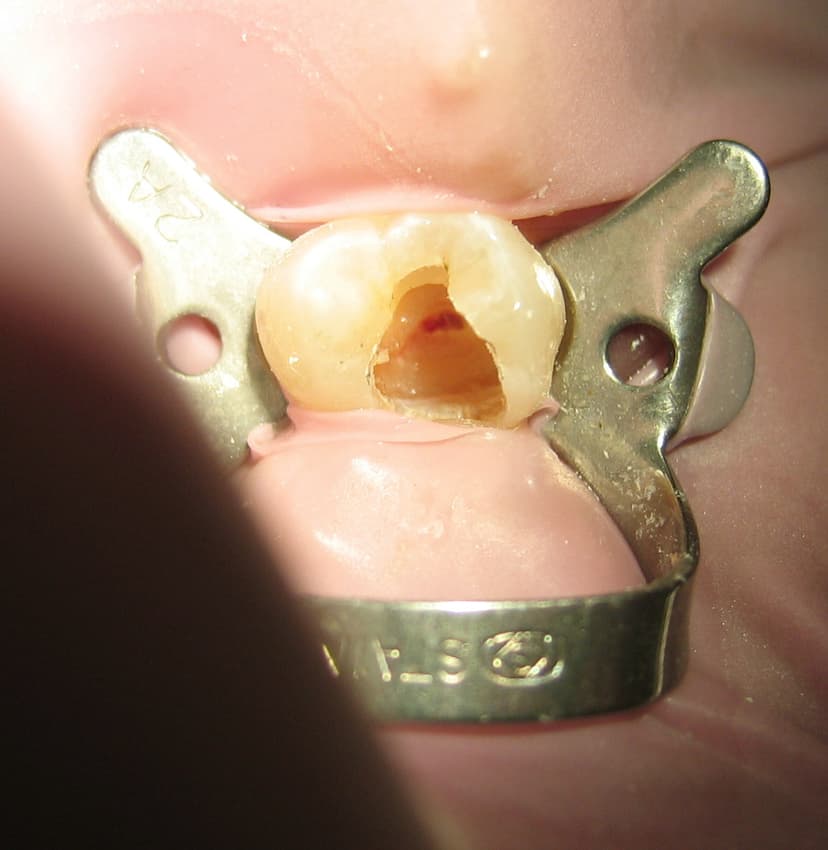

Root Canal Treatment: Why It’s So Misunderstood

Root canal treatment is often feared for the wrong reasons. This article explains why it’s misunderstood, how modern techniques have made it comfortable, and why timely treatment can save your natural tooth.